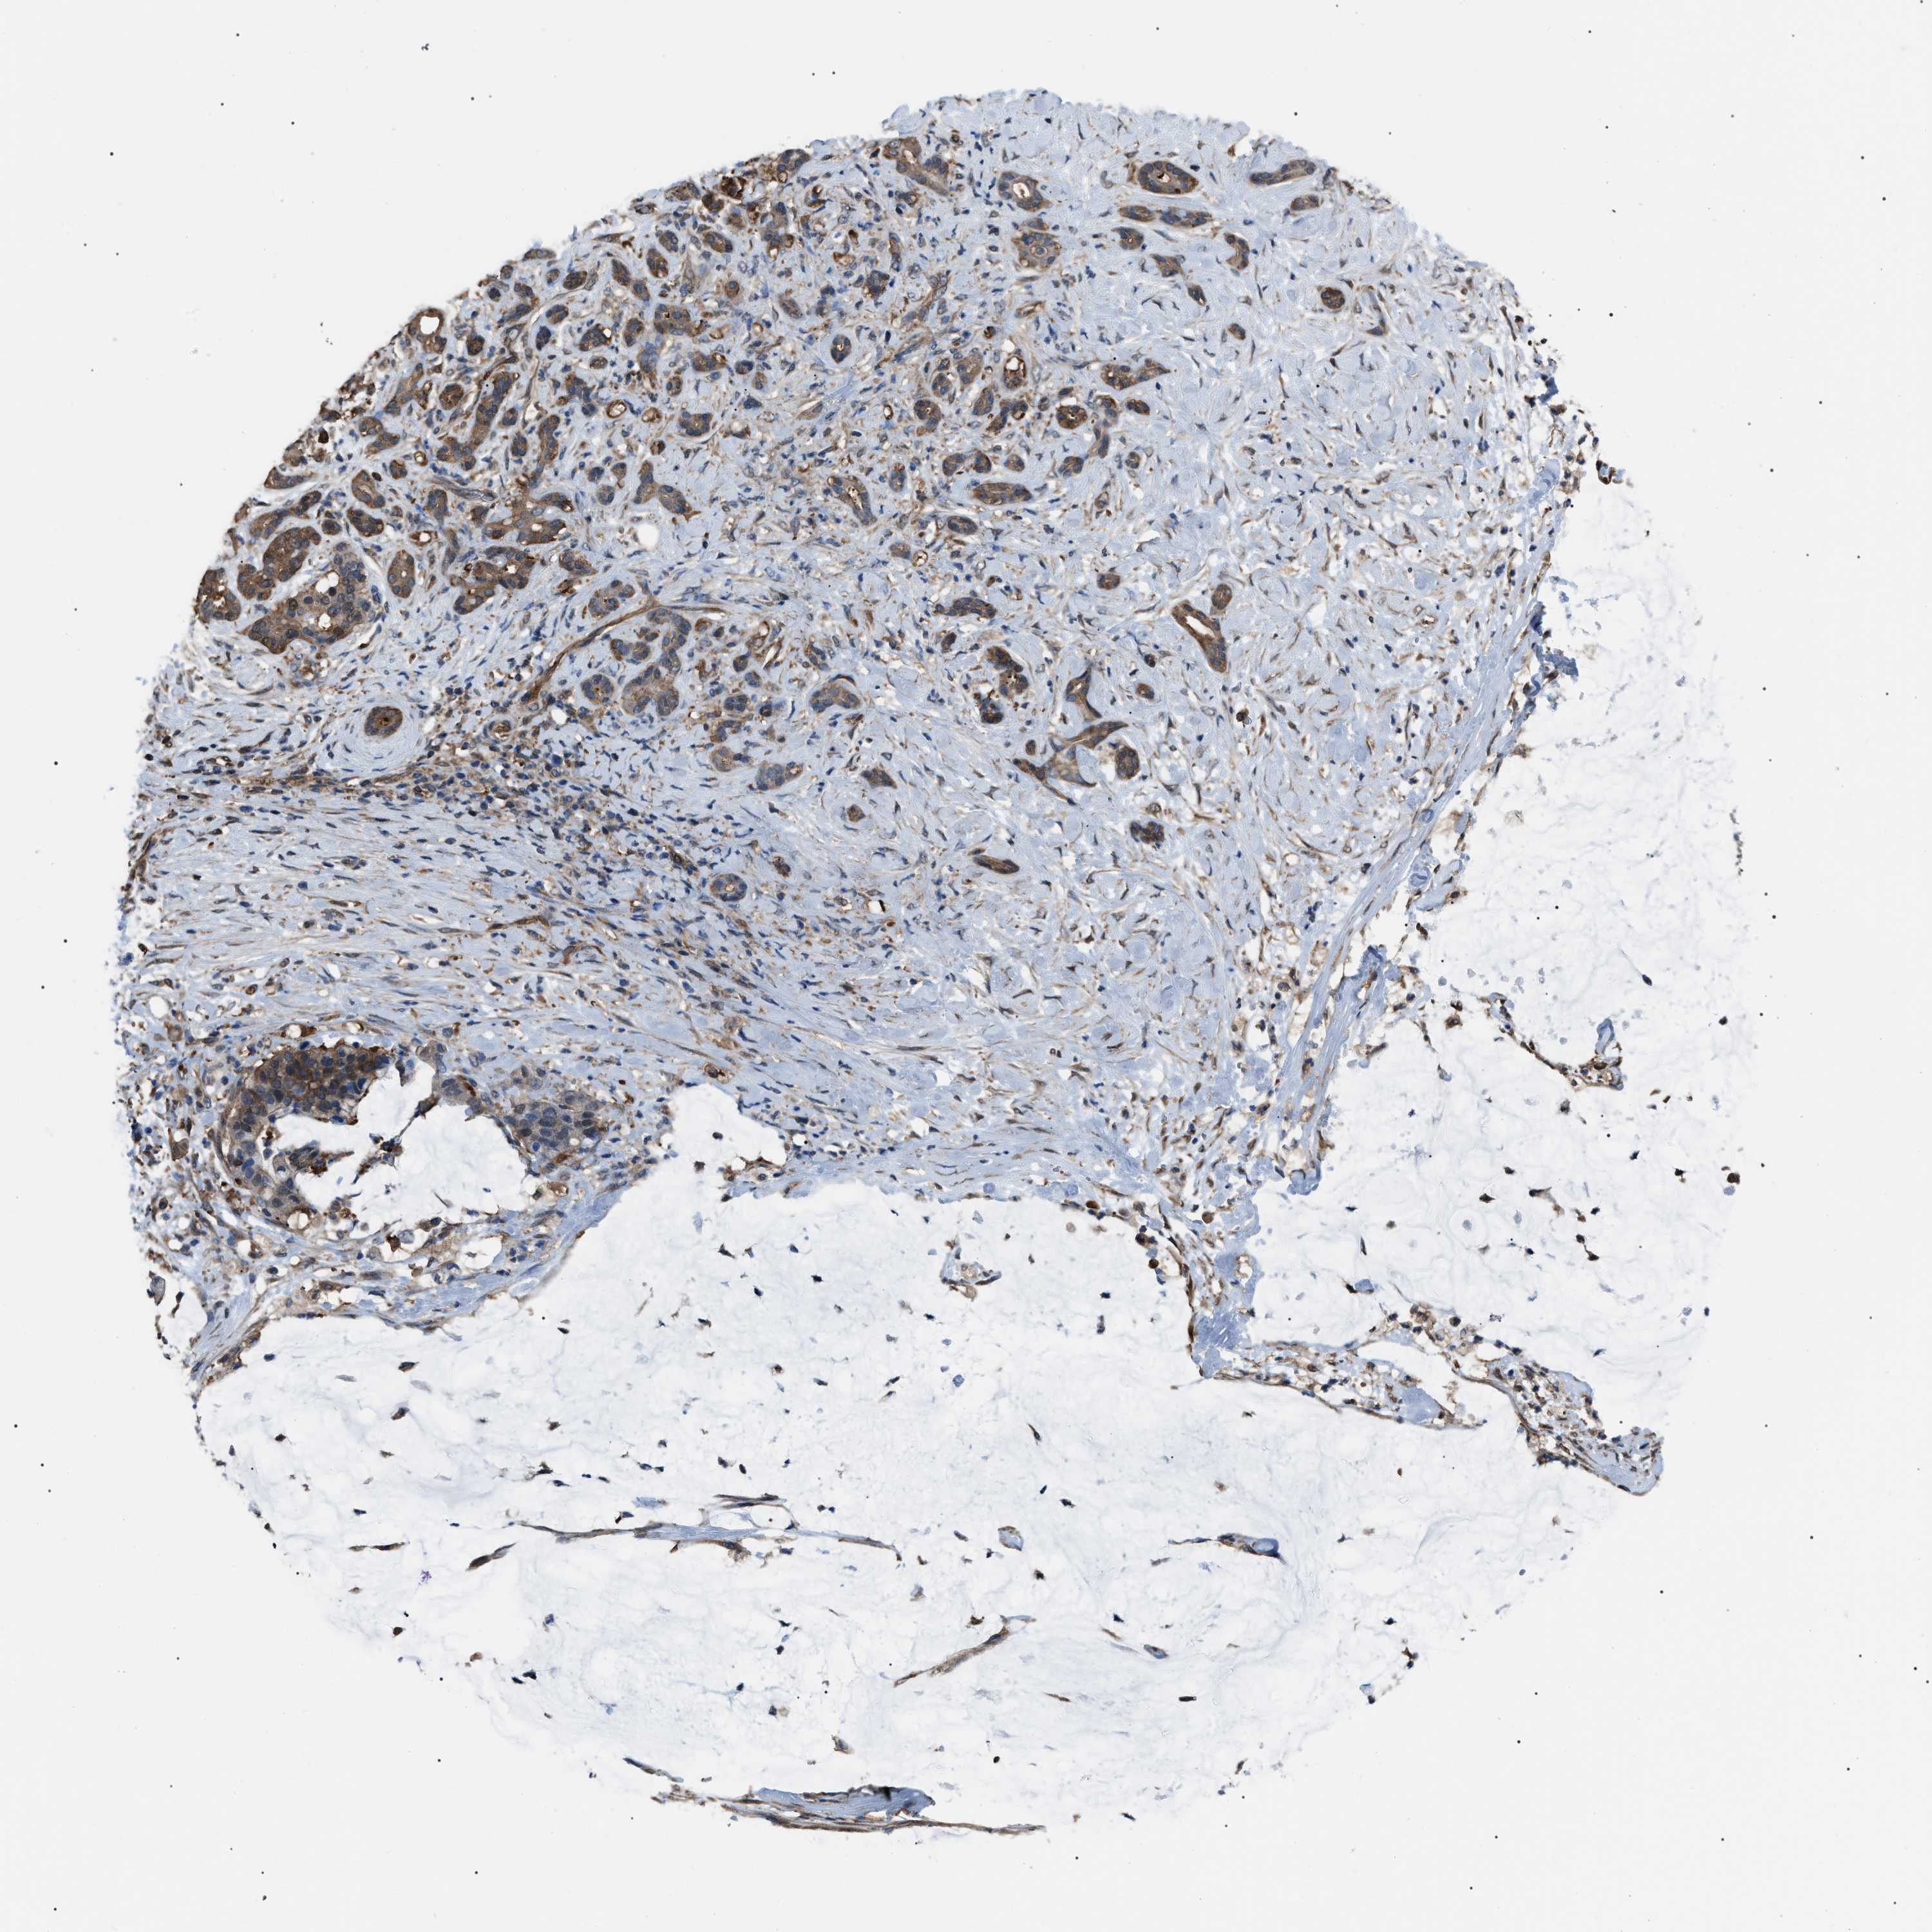

PANCREATIC CANCER - Protein expressioni

A mouse-over function shows sample information and annotation data. Click on an image to view it in a full screen mode. Samples can be filtered based on level of antibody staining by selecting one or several of the following categories: high, medium, low and not detected. The assay and annotation is described here.

Note that samples used for immunohistochemistry by the Human Protein Atlas do not correspond to samples in the TCGA dataset.

Antibody stainingi

Antibody staining in the annotated cell types in the current human tissue is reported as not detected, low, medium, or high, based on conventional immunohistochemistry profiling in selected tissues. This score is based on the combination of the staining intensity and fraction of stained cells.

Each image is clickable and will lead to virtual microscopy that enables deeper exploration of all samples and also displays staining intensity scores, fraction scores and subcellular localization as well as patient and tissue information for each sample.

Antibody HPA018471

Staining

High

Medium

Low

Not detected

Intensity

Strong

Moderate

Weak

Negative

Quantity

>75%

75%-25%

<25%

None

Location

Nuclear

Cytoplasmic/membranous

Cytoplasmic/membranous,nuclear

Adenocarcinoma, NOS